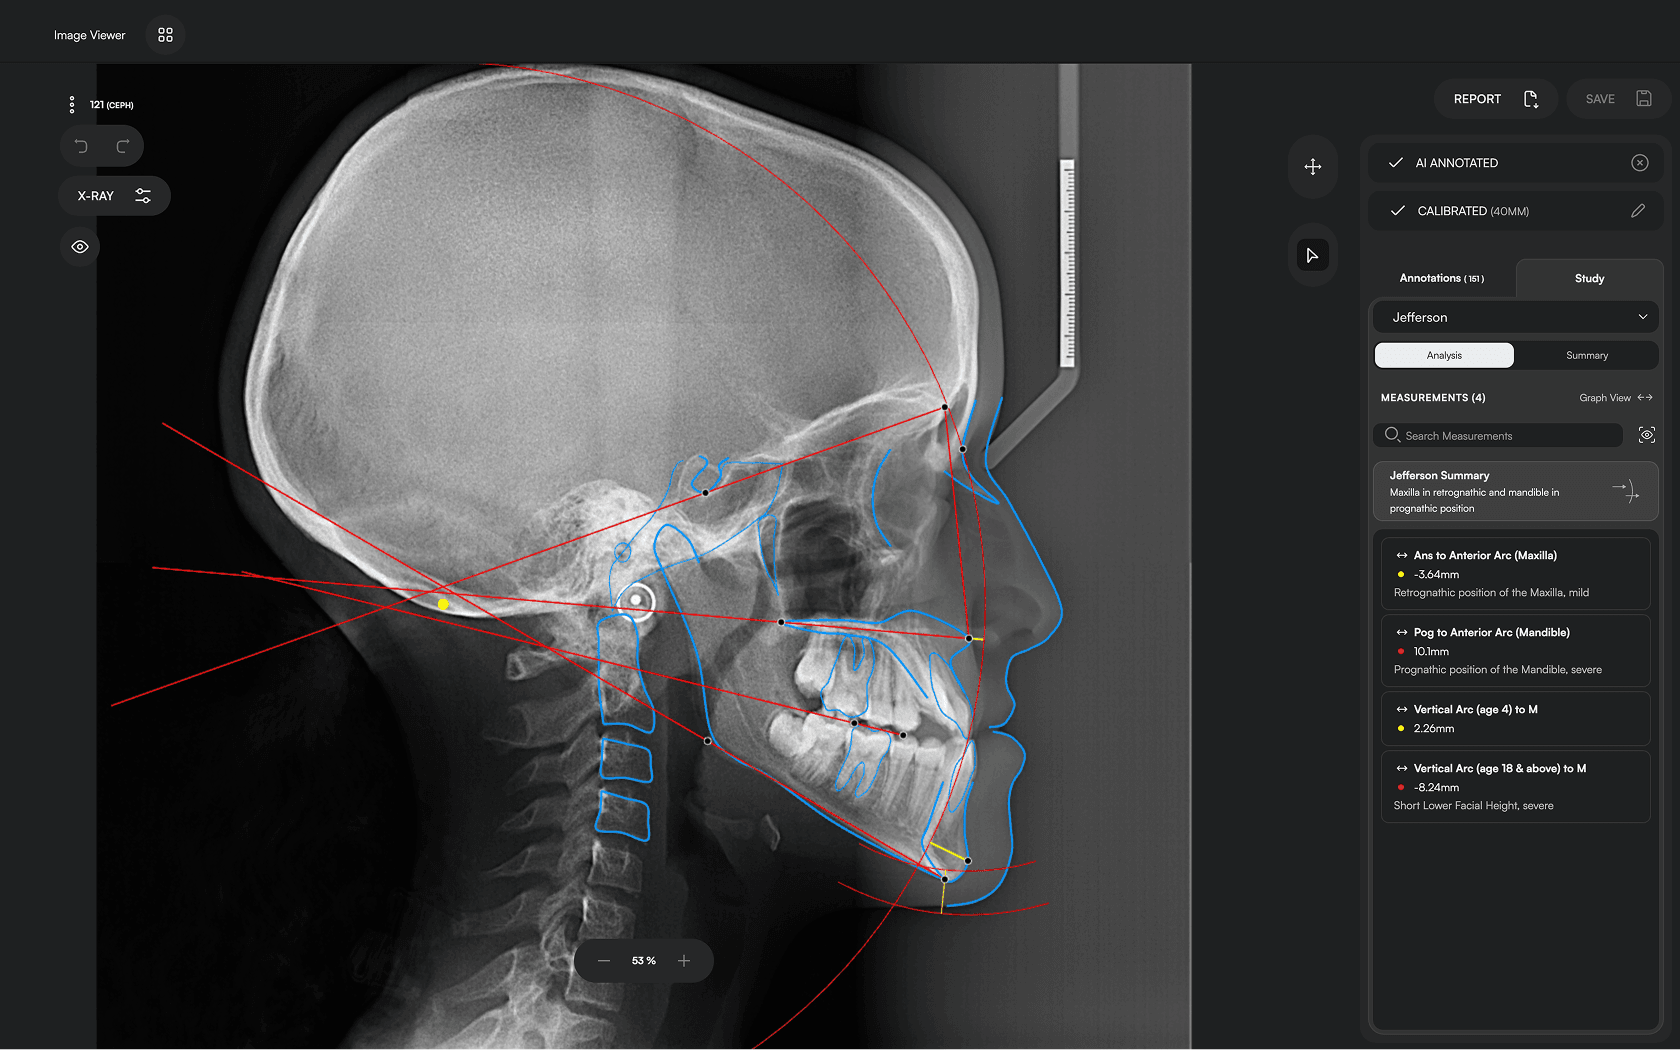

Diverse Analysis

Access automated studies like Steiner and Jefferson to assist in clinical assessment and enhance case evaluations.

Experience a comprehensive assessment of skeletal, dental, and soft tissue discrepancies.